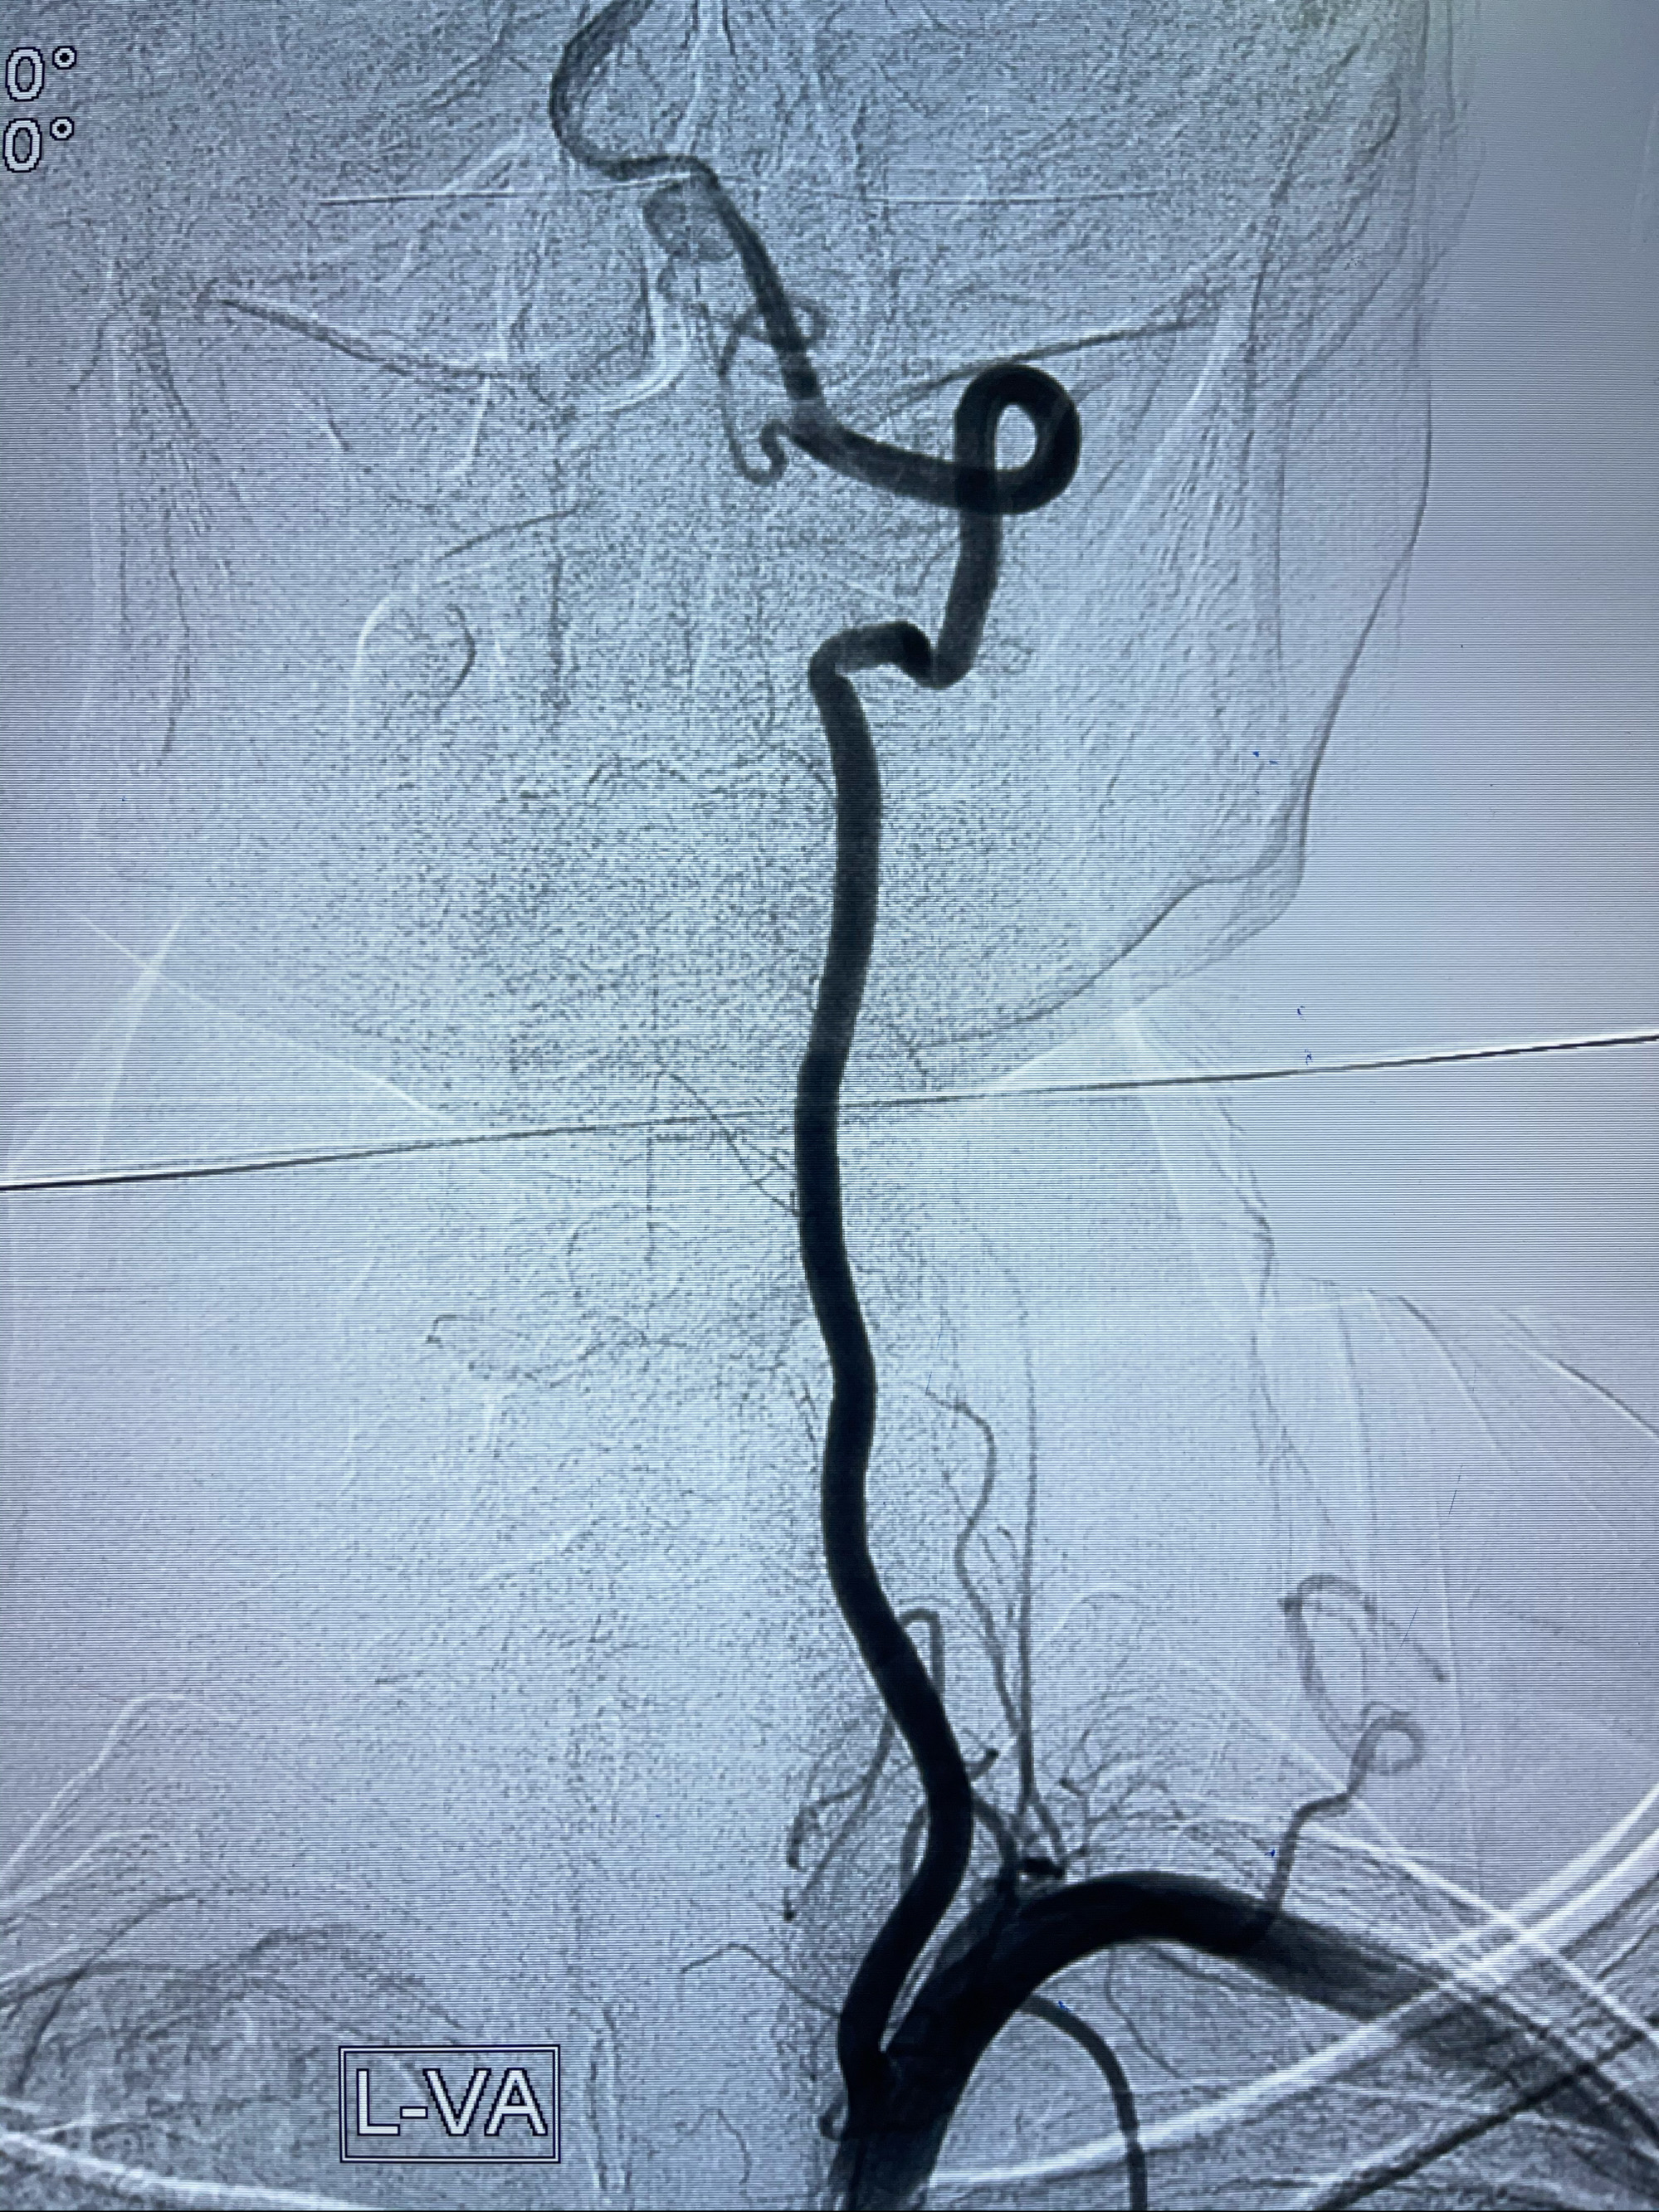

2021-03-08行全脑血管造影

左侧椎动脉V4夹层动脉瘤多支架辅助栓塞: